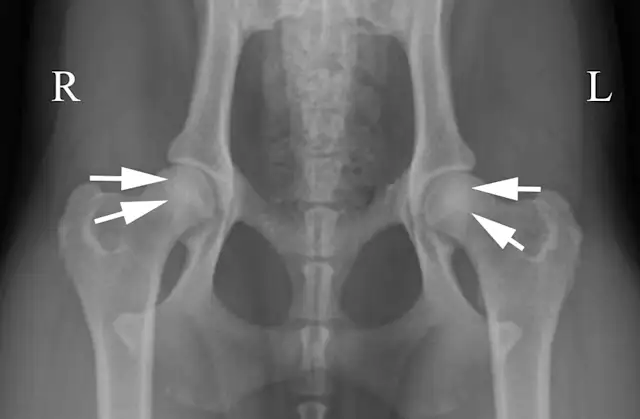

If the stifles are kept internally rotated, the patella should be centrally located over the distal femurs, as seen in the normally positioned radiograph (Figure 1B). In this image the femurs are parallel with each other and parallel with the imaging plate. Note the uniform and equal size of the obturator foramen on this well-positioned radiograph. Ideally, the sacrum, ilial wings, and entire 7th lumbar vertebra should be included in the image. Figure 1C shows an example of the pelvis correctly positioned.

Pelvic radiographs must be assessed for adequate positioning and should be repeated if the pelvis is oblique, as in Figure 2A. In this example, there are multiple positioning errors. The right femur/stifle should be further internally rotated (so the patella is more centrally located over the femur). The right stifle should be moved axially (medially) so the femurs are parallel. The pelvis is rotated with the right hemipelvis farther away from the imaging plate. In Figure 2B, the right hemipelvis has been elevated from the imaging plate. In this image, the right (up) obturator foramen is increased in width compared with the left. Additionally, the left (down) ilium appears narrower.

Oblique positioning will result in false assessment of dorsal acetabular rim coverage of the femoral head, as shown in Figure 2C. The dorsal acetabular rim (white arrows) appears to provide more coverage of the right femoral head and less coverage on the left side. When the patient is properly positioned, as in Figure 2D, it is evident that coverage of the dorsal acetabular rim (white arrows) is similar on both sides.